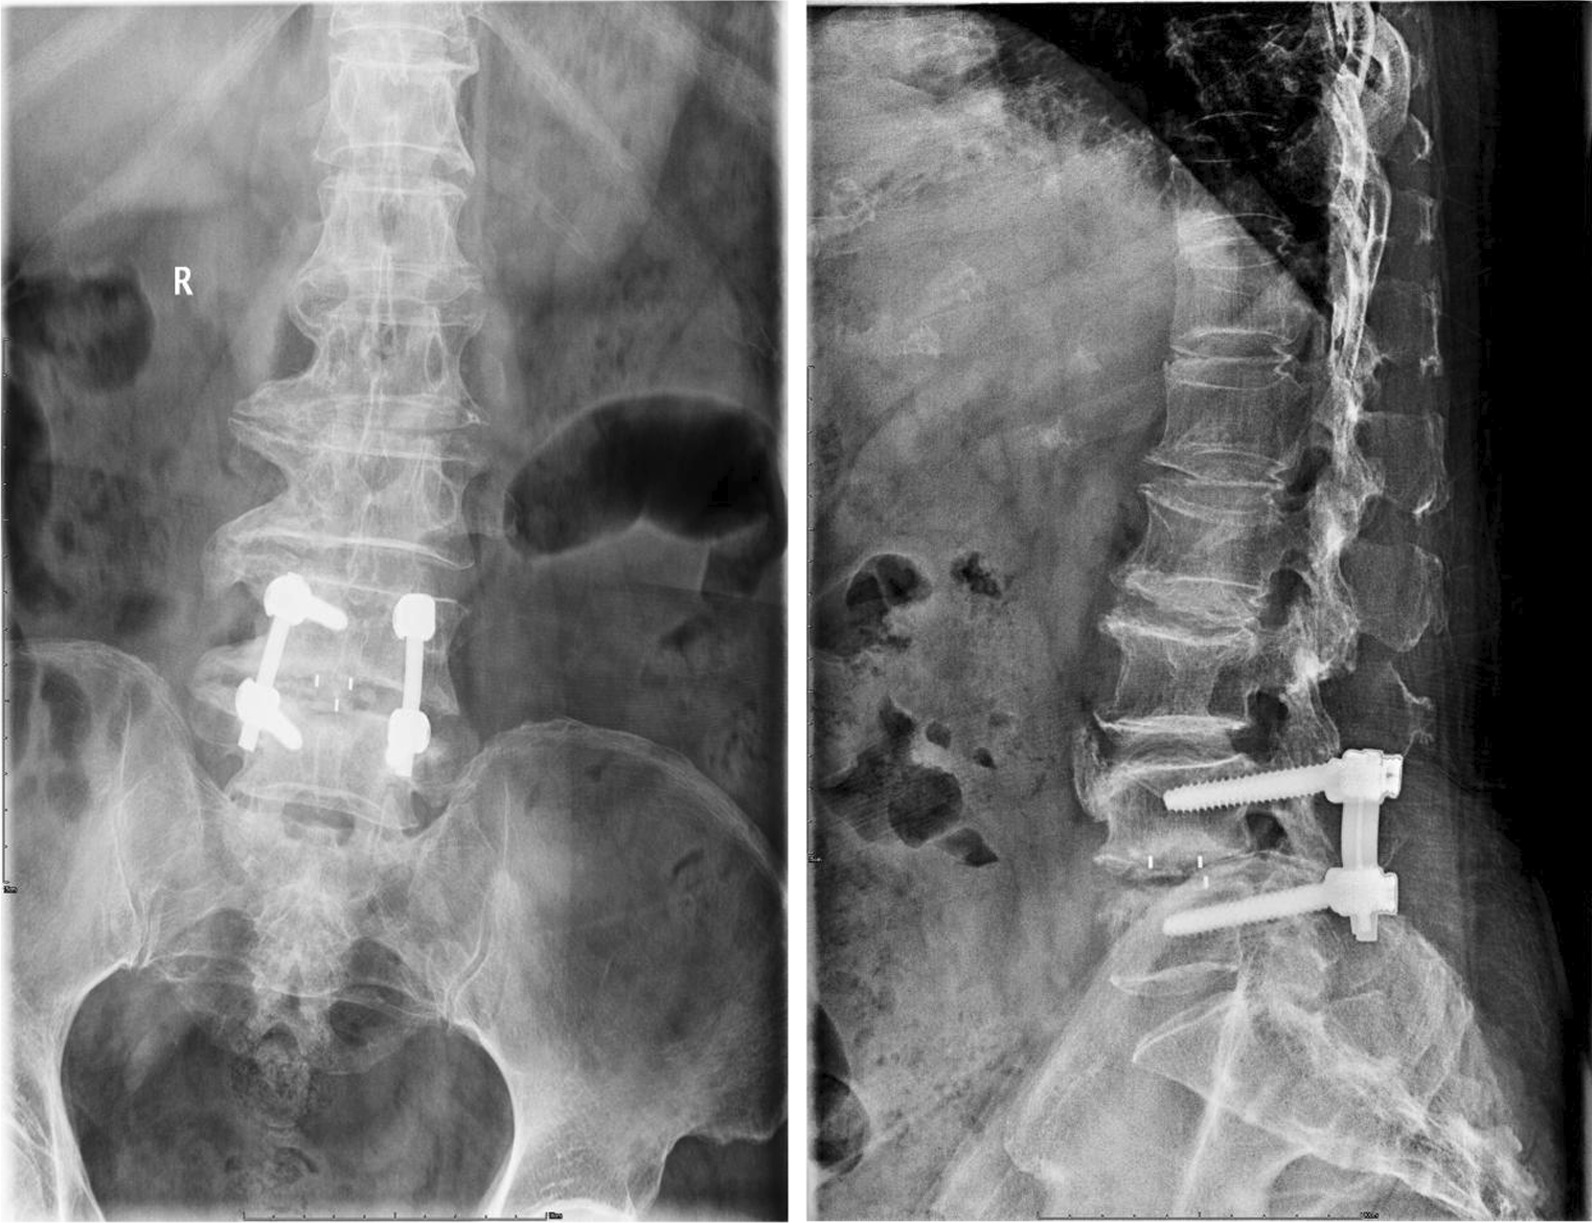

In determining fusion grades, each observer classified a case with three grades as definite fusion (grade I) (Fig. 5), non-union (III, IV), or probable fusion (II) (Fig. 6) using Bridwell’s fusion grading system [12]. A case with a definite finding was determined by the agreements of two observers. A case with a probable finding was determined by the agreement of two observers or by one observer’s decision of definite finding with another’s decision of probable (Fig. 7). The fusion rates with definite (86.7%) and probable (6.7%) grades in the BLIF group were higher than that in the ULIF group (definite: 70% and probable: 3.3%), with a statistically significant difference (P < 0.05) (Table 8). One case of cage subsidence with no screw loosening occurred in each group; thus, there was no obvious difference between the two groups (P > 0.05) (Table 9).

Fig. 6.

One of the “probable fusion” cases